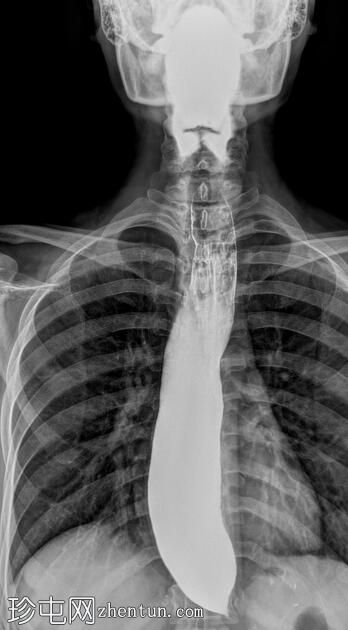

正位

食管扩张,远端平滑狭窄并呈锥形(鸟嘴状),符合贲门失弛症的特征性表现

食管黏膜形态正常,无异常或溃疡

未见食管裂孔疝

钡餐检查显示食管扩张,远端狭窄并呈锥形,形成符合贲门失弛症特征的鸟嘴状外观。